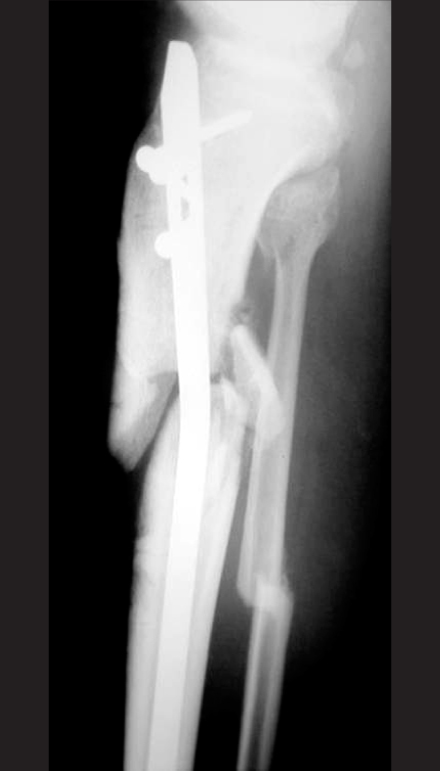

Fig. 1

Radiographs show a healed fracture of the proximal tibia with valgus deformity and apex anterior deformity after locked nail.

Fig. 1 Radiographs show a healed fracture of the proximal tibia with valgus deformity and apex anterior deformity after locked nail.